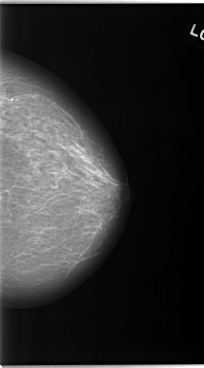

C_0046_1.LEFT_CC

LEFT_CC LINES 5880 PIXELS_PER_LINE 3264 BITS_PER_PIXEL 12 RESOLUTION 50 NON_OVERLAY